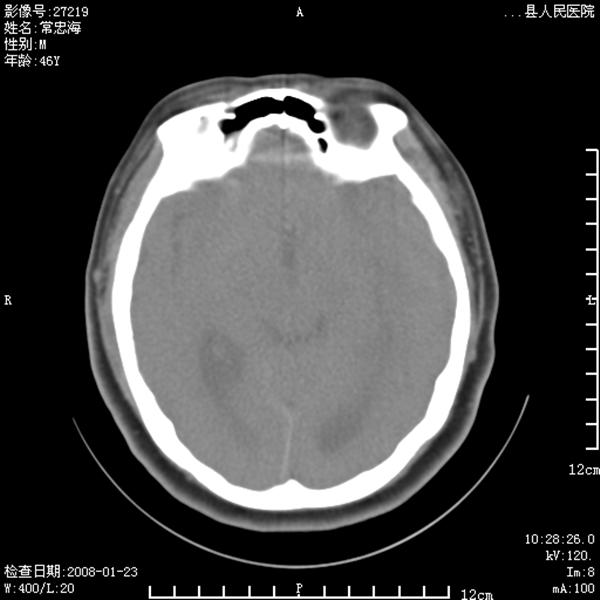

以下是引用江边学者在2008-4-19 22:26:00的发言:[br]1.胼胝体发育不良。[br]2.右侧眼球痨。[br]3.右侧颜面部软组织挫伤。